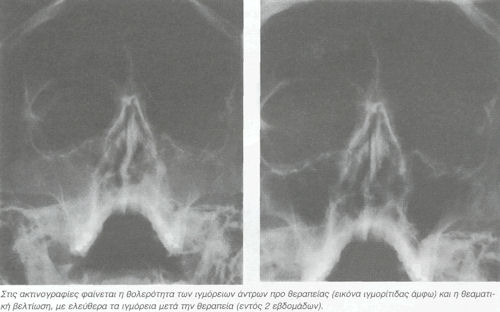

Πρόκειται για άντρα 40 ετών που εμφάνισε μπούκωμα-κιτρινοπράσινο έκκριμα από την μύτη και καταρροή πυκνού ιξώδους υγρού. Είχε έντονη συμπτωματολογία που ξεκινούσε από τον αυχένα με πόνο και πιάσιμο και επεκτεινόταν στο μέτωπο και στο βρέγμα.

Πήρε Kali Bichromicum 200 CH τρεις δόσεις και είχε βελτίωση έως εξαφάνιση των συμπτωμάτων. Μετά από μία εβδομάδα υπήρξε υποτροπή με τα ίδια συμπτώματα που αντιμετωπίστηκε με δύο δόσεις Kali Bichromicum 200 CH με θεαματική βελτίωση και εξαφάνιση των συμπτωμάτων.

Έκτοτε είναι ελεύθερος συμπτωμάτων από τους παραρρινίους κόλπους (ιγμόρεια) και τον αυχένα.